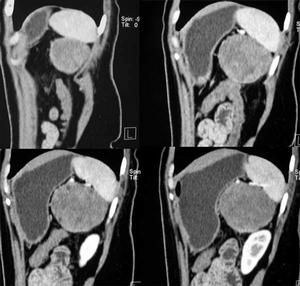

侵蝕性葡萄胎3.超聲檢查B型超聲為非侵入性檢查,可以早期發現葡萄胎組織侵入子宮肌層程度,協助診斷子宮內滋養細胞腫瘤病灶。宮壁顯示局灶性或瀰漫性強光點或光團與暗區相間的蜂窩樣病灶,應考慮為侵蝕性葡萄胎或絨癌。

4.組織學診斷單憑刮宮標本不能作為侵蝕性葡萄胎的診斷依據,但在侵入子宮肌層或子宮外轉移的切片中,見到絨毛結構或絨毛退變痕跡,即可診斷為侵蝕性葡萄胎。若原發灶與轉移灶診斷不一致,只要任一標本中有絨毛結構,即應診斷為侵蝕性葡萄胎。